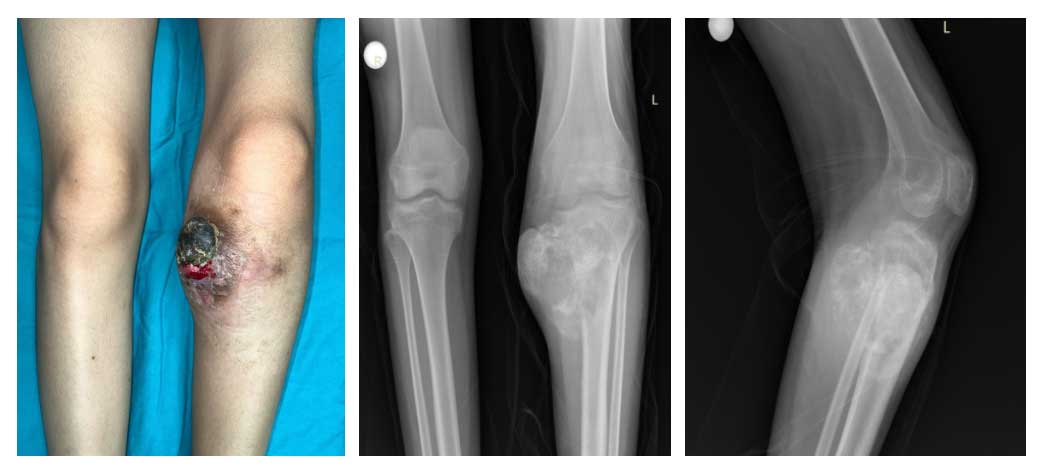

Ameliyat Öncesi: Tümörün klinik ve Röntgende proksimal tibia medialde ciddi harabiyete neden olan ve yumuşak dokuya uzanan düzensiz sınırlı ve heterojen görüntüsü.